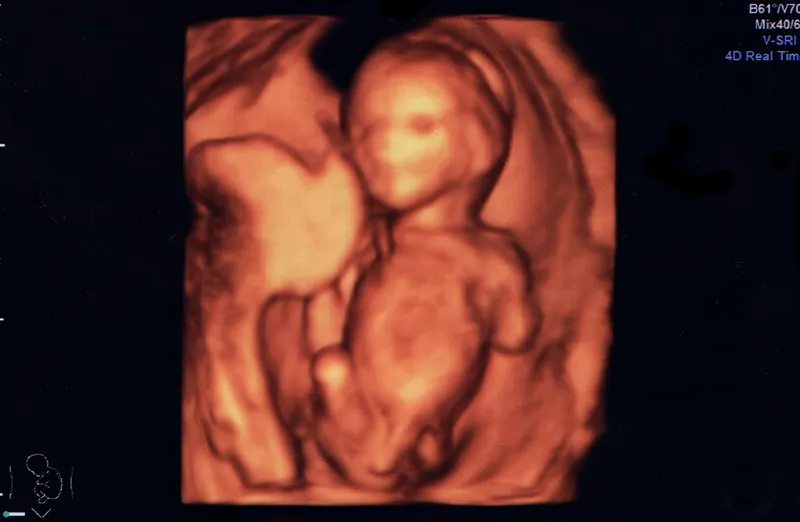

3D4Dエコー

5,500円(税込)

GEヘルスケアのボルソンE10にて3D4Dエコーをお受けいただけます。